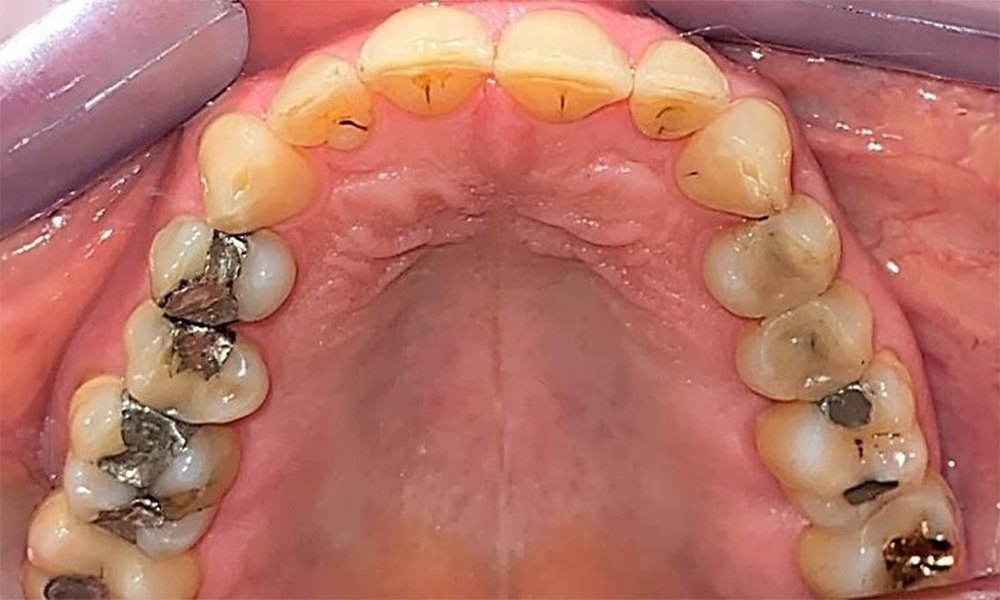

Der Patient hat ein vollbezahntes Gebiss mit 28 Zähnen, an welchen sich im Molaren- und Prämolarenbereich Amalgamfüllungen und Compositefüllungen befinden. An Zahn 14 zeigt sich ein sichtbarer klinischer Randspalt. Zahn 27 hat ein suffizientes Goldinlay. Zudem zeigen sich generalisierte Attritionen und Abrasionen. (Abb. 2, Abb. 3, Abb. 4, Abb. 5, Abb. 6)

Der Patient hat eine Parodontitis Stadium II, Grad B (5). Die klinischen Sondierungstiefen liegen mit 1-3mm im physiologischen Bereich. Lokalisierte Sondierungstiefen finden sich an 17 und 27 jeweils mesiopalatinal mit 5mm. Es liegen generalisierte Rezessionen von 1-3mm vor mit partiellem Verlust der Interdentalpapillen (Abb. 2, Abb. 3, Abb. 4)